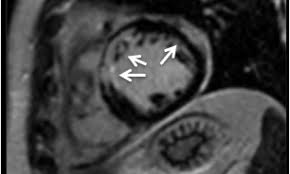

Das bildgebende verfahren ermöglicht zudem die beurteilung des schweregrades der myokardialen entzündung und der begleitenden funktionsstörung sowie die objektivierung des verlaufes der erkrankung unter therapie, berichtet prof. Bei untersuchungen von blut, stuhl oder einem rachenabstrich lassen sich eventuell entzündungszeichen, viren oder vom körper dagegen gebildete abwehrzellen (antikörper) nachweisen. Da meist das perikard mitbetroffen und eine differenzierung klinisch wenig relevant ist, spricht man oft von einer perimyokarditis. Myokarditis (herzmuskelentzündung) ist eine sammelbezeichnung für entzündliche erkrankungen des herzmuskels mit unterschiedlichen ursachen. In seltenen fällen offenbart sich das krankheitsbild dramatisch, ähnlich einem. Patientinnen und patienten erhalten über eine vene eine kleine menge des kontrastmittels gadolinium. Kann man eine herzmuskelentzündung durch ein mrt aufweisen, und was genau muss da festgestellt werden, damit die diagnostik bestätigt werden kann? Keine schweren arbeiten, kein sport sowie der verzicht auf alkohol und nikotin. Im vordergrund steht hier die körperliche schonung. Im zuge dessen stechen die entzündungsherde hervor. Antwort auf diese frage gibt eine aktuelle studie. Mrt ermöglicht diagnose und verlaufskontrolle bei myokarditis nur die kombination mehrerer sequenzen bringt die erforderliche genauigkeit die myokarditis ist eine tückische erkrankung: Man findet örtlich im herzmuskel schwellungen, gewebszerstörungen oder vernarbungen.

Die besten anhaltspunkte für krankhafte vorgänge im herzmuskel liefert die kernspinuntersuchung herzmuskelentzündung. Erste hinweise geben wandbewegungsstörungen und einschränkungen der pumpfunktion.